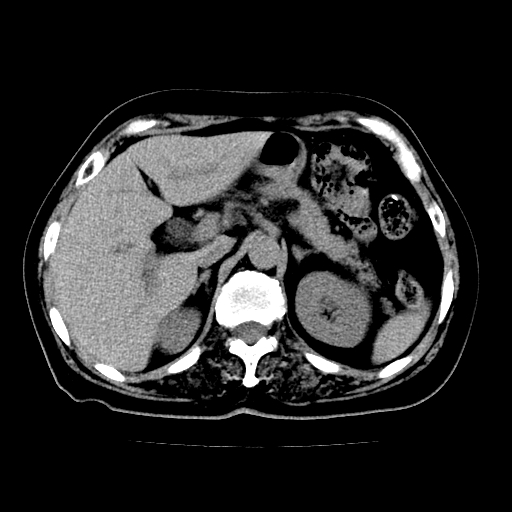

以下是引用lujiandong在2009-2-8 9:37:00的发言:[br]从所发的ct平扫图象上看,胆总管明显增粗,从上向下逐渐变细,是否有泥沙样结石,建议薄层重建;胰腺形态基本正常,左侧肾前筋膜轻度增厚。可以考虑:轻度单纯性胰腺炎,建议ct增强扫描。